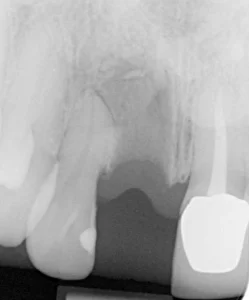

This woman had a badly broken down lower molar that had split apart and had been painfully abscessing for months. Unfortunately, it was beyond saving, and it was extracted. Keen to have the space restored, the patient opted to have an implant placed.

Below shows the crown fitted on to the implant post.